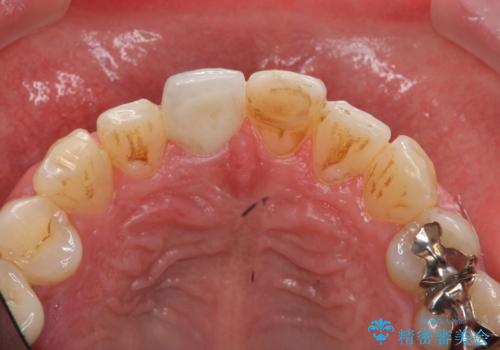

前歯の変色を改善 オールセラミック治療

- 目立つ前歯の変色の改善を希望され来院されました。

根管治療を行いそのままにしていると歯は、徐々に変色を来します。

感染の疑われる根管内に対し再度根管治療を行い、セラミッククラウンを作製することで審美性の回復します。